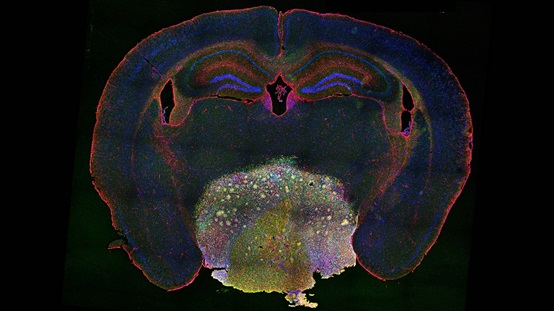

Mouse craniopharyngioma (Image by IGDB)

In 2021, Professor WU identified the cellular origins of papillary craniopharyngioma. Building on this achievement, he and his team developed two sophisticated animal models that faithfully recapitulate the imageological, histological, phenomic, and transcriptomic characteristics of human craniopharyngioma. These models successfully mimic the pathological progression observed in patients, providing an invaluable platform for studying tumorigenic mechanisms and developing therapeutic interventions.

While bulk, single-cell and spatial transcriptomic analyses revealed an enriched transcriptional program related to synaptic transmission in the mouse tumors, their immunostaining and electron microscopic results further demonstrated synaptic contacts between hypothalamic neurons and tumor cells. Using chemogenetic techniques, the researchers modulated the activity of hypothalamic neuroendocrine neurons in their animal models. They found that enhanced neuronal activity accelerated tumor growth, while reduced activity inhibited it.